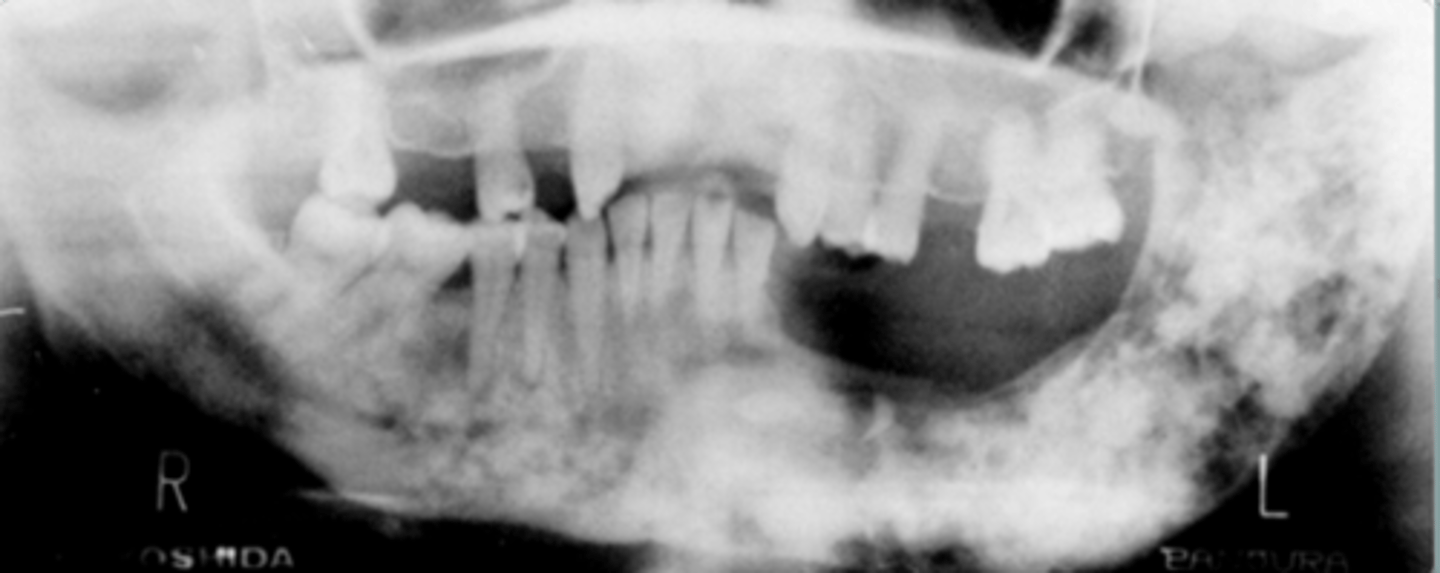

Pericoronitis

inflammation around the crown of a partially erupted tooth

Where is pericoronitis commonly found?

third molars

Radiographic features of pericoronitis

underlying osteitis

loss of cortical outline